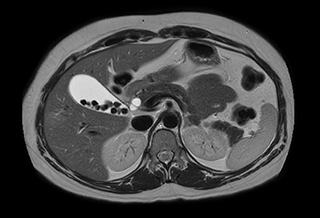

Subtractionless MRA run-off studies with exceptional spatial and temporal resolution

“In our peripheral MRA run-off studies with Ambition we realize key benefits, including outstanding image quality and significantly reduced breath-hold and scan times, which not only benefit the patient, but also provide the opportunity to add sequences that could aid in diagnosis,” Dr. Peña says.

“Before we had Ingenia Ambition, our CE-MRA run-off studies would first acquire a dynamic pre-contrast scan with 20-25-second breath-holds, then inject the contrast, do another acquisition and then subtract the two,” says Avila. “Now, mDIXON XD allows us to complete the study in just one single pass – without need for a pre-exam – which eliminates subtraction artifacts and almost halves the scan time. In addition, mDIXON provides much better background suppression, which really improves vesselto-background contrast. And, thanks to Compressed SENSE, the single breath-hold is not long and we improve image resolution.”

“Because mDIXON XD provides subtractionless fat-free imaging, we get much better background suppression, which really helps the vessels stand out”

MRA run-off study with mDIXON

The subtractionless peripheral MR angiography shows improved vessel-to-background contrast and high resolution. Ingenia Ambition 1.5T.

Station

Ingenia Ambition

Pelvis

Voxels 1.3 x 1.3 x 3.2 mm, FOV 430 mm, 125 slices

Upper legs

Lower legs

Voxels 1.0 x 0.82 x 2.0 mm, FOV 430 mm, 125 slices